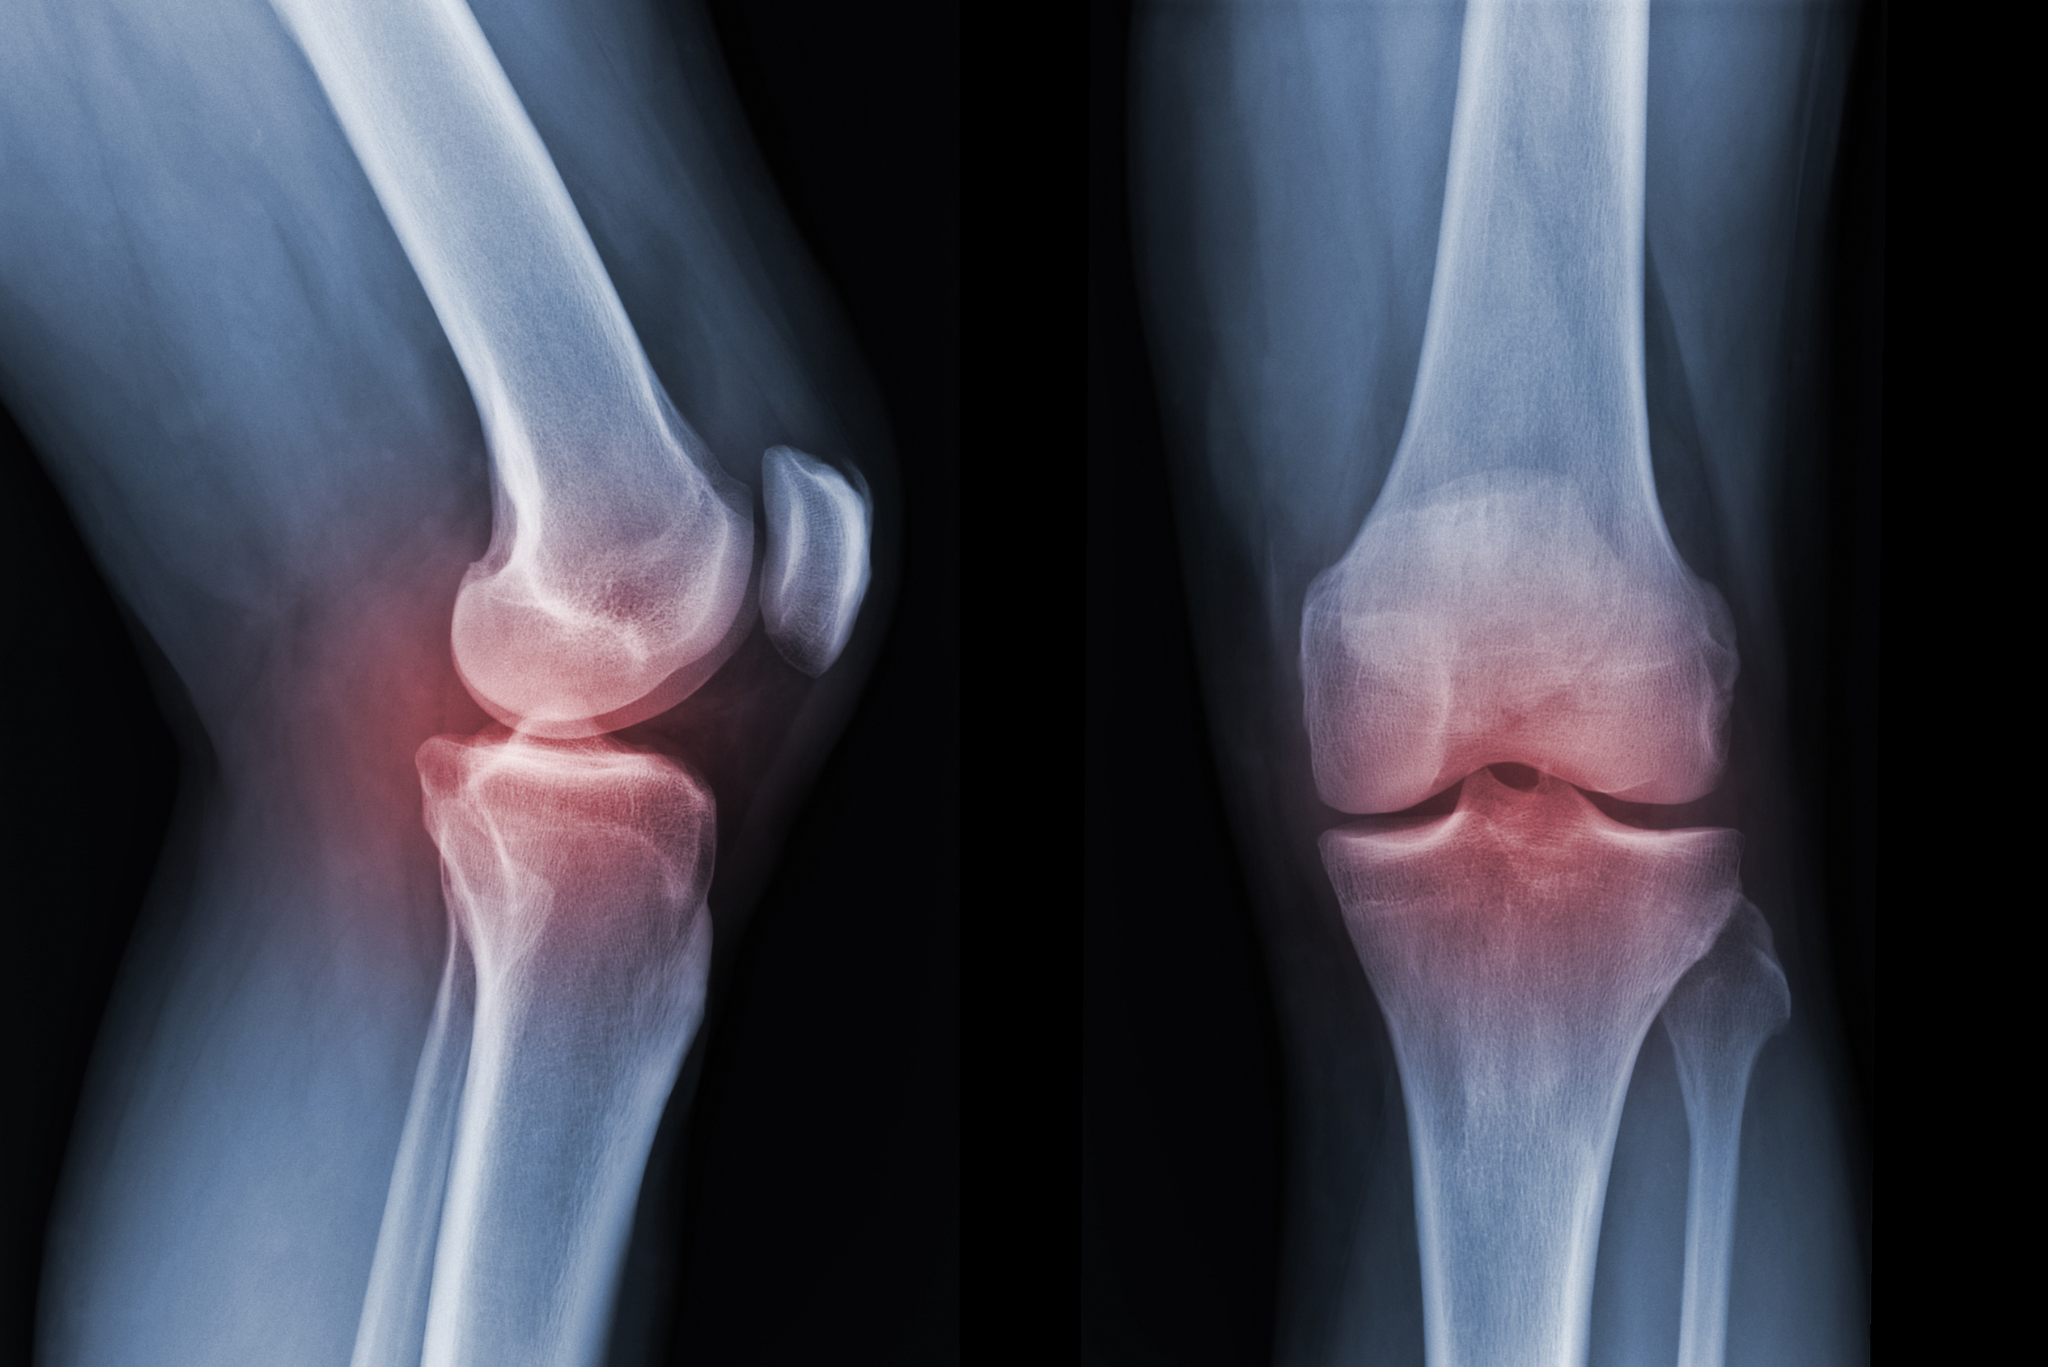

Orthopedic conditions can affect your bones, joints, muscles, tendons, and spine — often leading to pain, reduced mobility, and a lower quality of life. Recognizing the signs early can help prevent further damage and improve recovery outcomes.